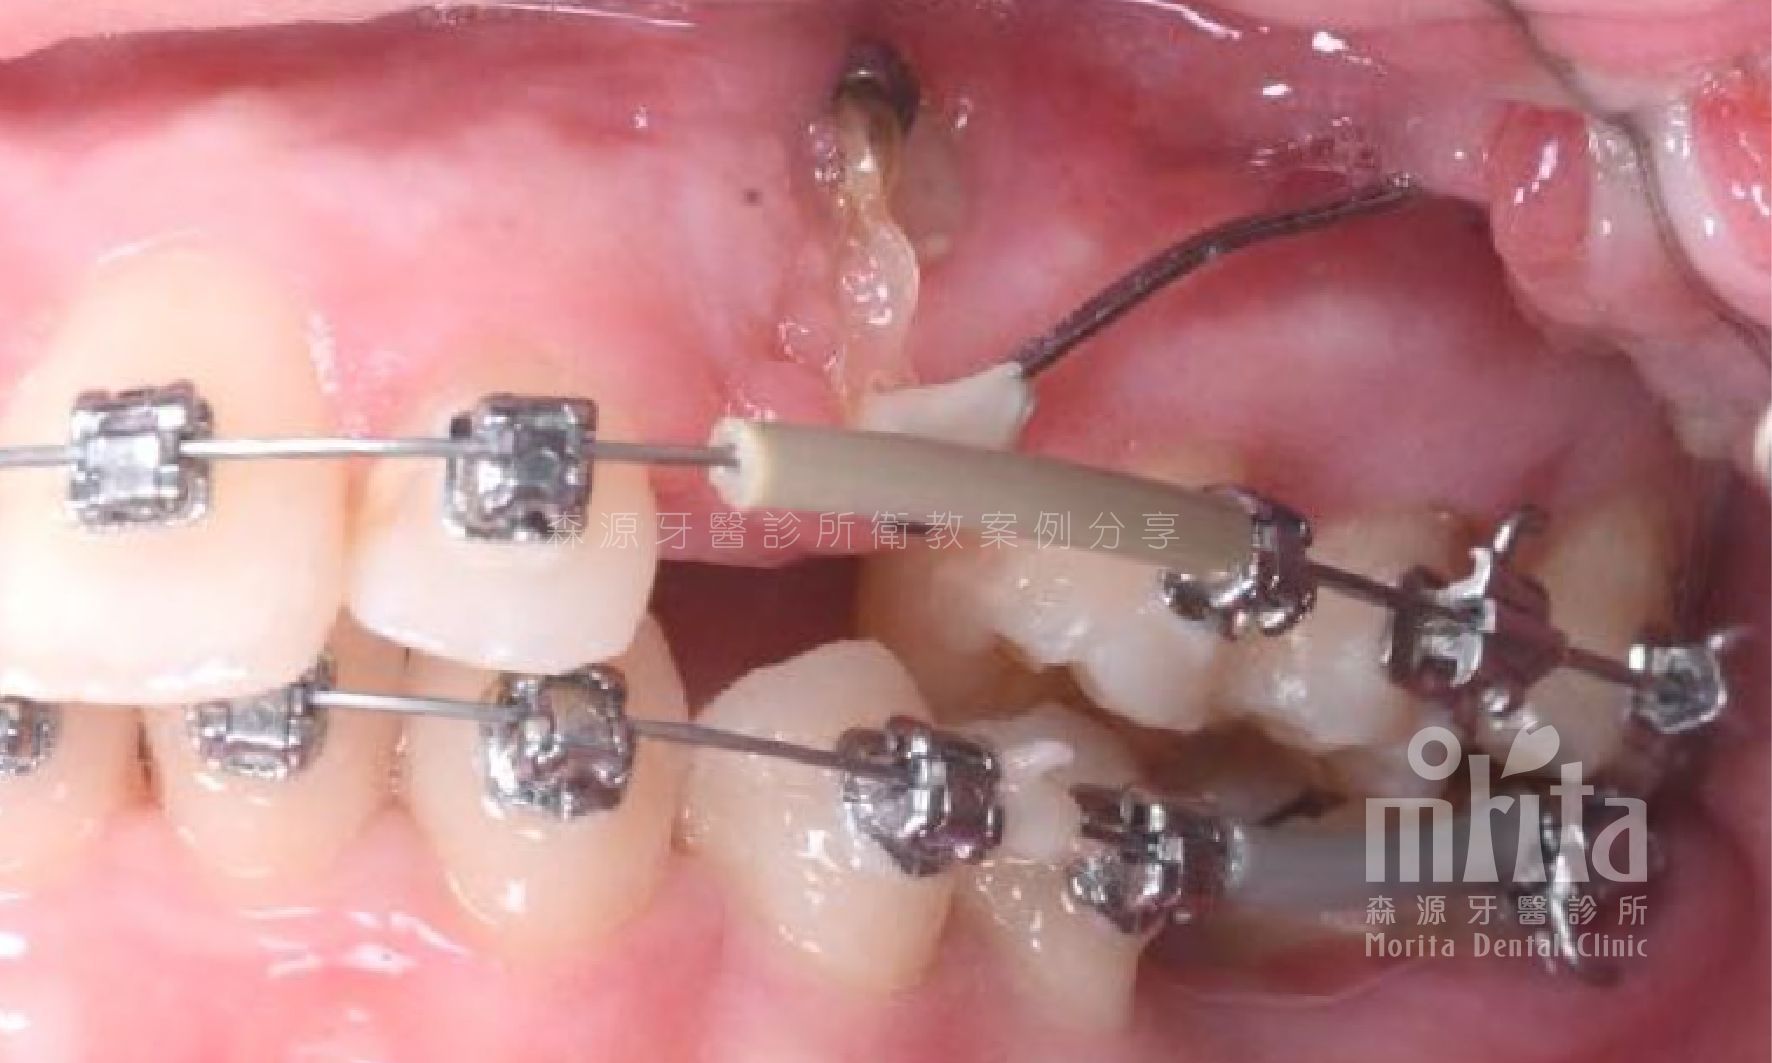

可能因為過早地缺牙,可能因為齒列過於擁擠,又或是老天爺開的玩笑,造成有些該⻑出來的牙齒⻑不出來,需要在阻生齒還有生⻑潛力時拉一把,讓牙齒順利萌發。

阻生齒 Impaction